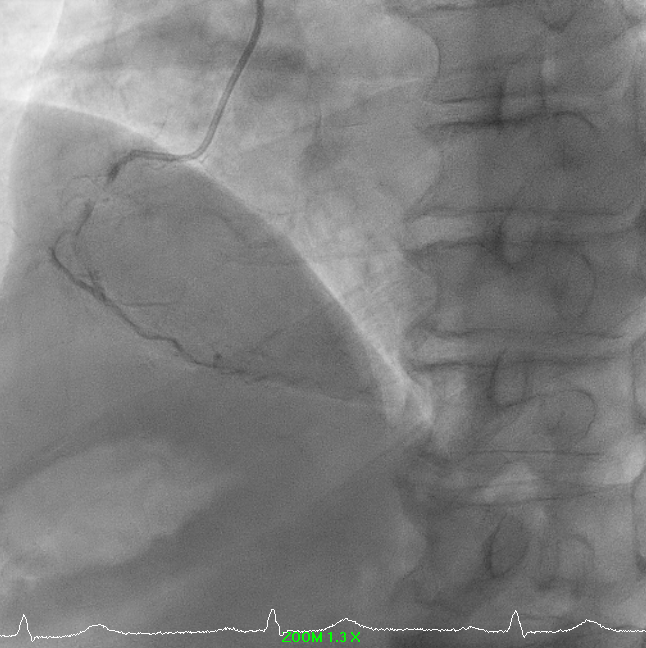

PCI to RCA CTO ISR: A PCI was performed for RCA chronic total occlusion in-stent restenosis (ISR) in a patient with ischemic cardiomyopathy, reduced LVEF, and moderate inducible ischemia. Femoral access was obtained using EBU (USG-guided, single attempt) and RRA 7F exchange. Initial crossing attempt with Corsair Pro XS/Fielder XTR failed; the lesion was successfully crossed using Fielder XTA, confirmed by retrograde angiography. Microcatheter was removed using the balloon trapping technique.

Predilation was challenging due to poor support. Initial 0.75 mm balloon could not pass; support was augmented with Sion Blue to RV branch. Subsequent predilation was performed sequentially with Zinrai 0.75 ¡¿ 4 mm, Ryureo 1.0 ¡¿ 5 mm, and NC balloon 2.0 ¡¿ 15 mm, achieving satisfactory antegrade flow. IVUS assessment demonstrated a distal vessel diameter of 2.5 mm, proximal/mid 3.5 mm, previous MSA 3.5 mm, and 360¡Æ proximal calcium. Additional predilation using Wedge 2.5 ¡¿ 15 mm (distal¡æproximal) and Scoreflex 3.0 ¡¿ 15 mm (mid¡æproximal) resulted in <30% recoil and no dissection. Post-IVUS, MSA improved from 3.5 ¡æ 4.8 mm.

A drug-coated balloon strategy was employed: Prevail 2.5 ¡¿ 30 mm @ 8 ATM ¡¿ 60s and Selution SLR 3.0 ¡¿ 35 mm @ 6 ATM ¡¿ 60s. Final angiography showed TIMI 3 flow with no residual dissection. The case highlights a complex RCA ISR-CTO managed successfully with a contemporary DCB-based, stent-less strategy guided by IVUS and meticulous lesion preparation.